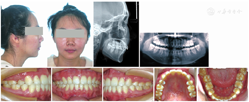

矫治后患者上下牙列排列整齐;双侧尖牙磨牙中性关系,咬合关系良好;前牙覆

、覆盖正常,上牙列中线居中,下牙列中线稍右偏;软组织侧貌前突得到改善;全口曲面断层片示牙列排列正常,牙根形态完好(图4)。

本病例为双牙弓前突病例,ANB角8.5°,高角。患者拒绝手术,希望通过单纯的正畸治疗代偿Ⅱ类骨骼关系,改善侧貌。患者的磨牙关系表现为中性关系,左侧尖牙中性关系,右侧尖牙略偏远中关系,上颌无明显拥挤,下颌前牙区轻度拥挤。为了较大程度改善患者侧貌,拔牙方案确定为拔除上下颌双侧第一前磨牙。

疗程上因患者治疗期间工作地点发生变动,复诊不便,复诊间隔延长,该病例完成历时32个月。但从治疗结果来看,患者前牙大幅度内收,侧貌观呈直面型,治疗前后头影测量重叠图(图5)可见磨牙无明显前移,磨牙支抗得到了很好的控制。由该病例可见,PASS技术结合种植钉支抗能高效控制前牙转矩,对前牙需要大量内收及控根移动的病例具有较好的效果。